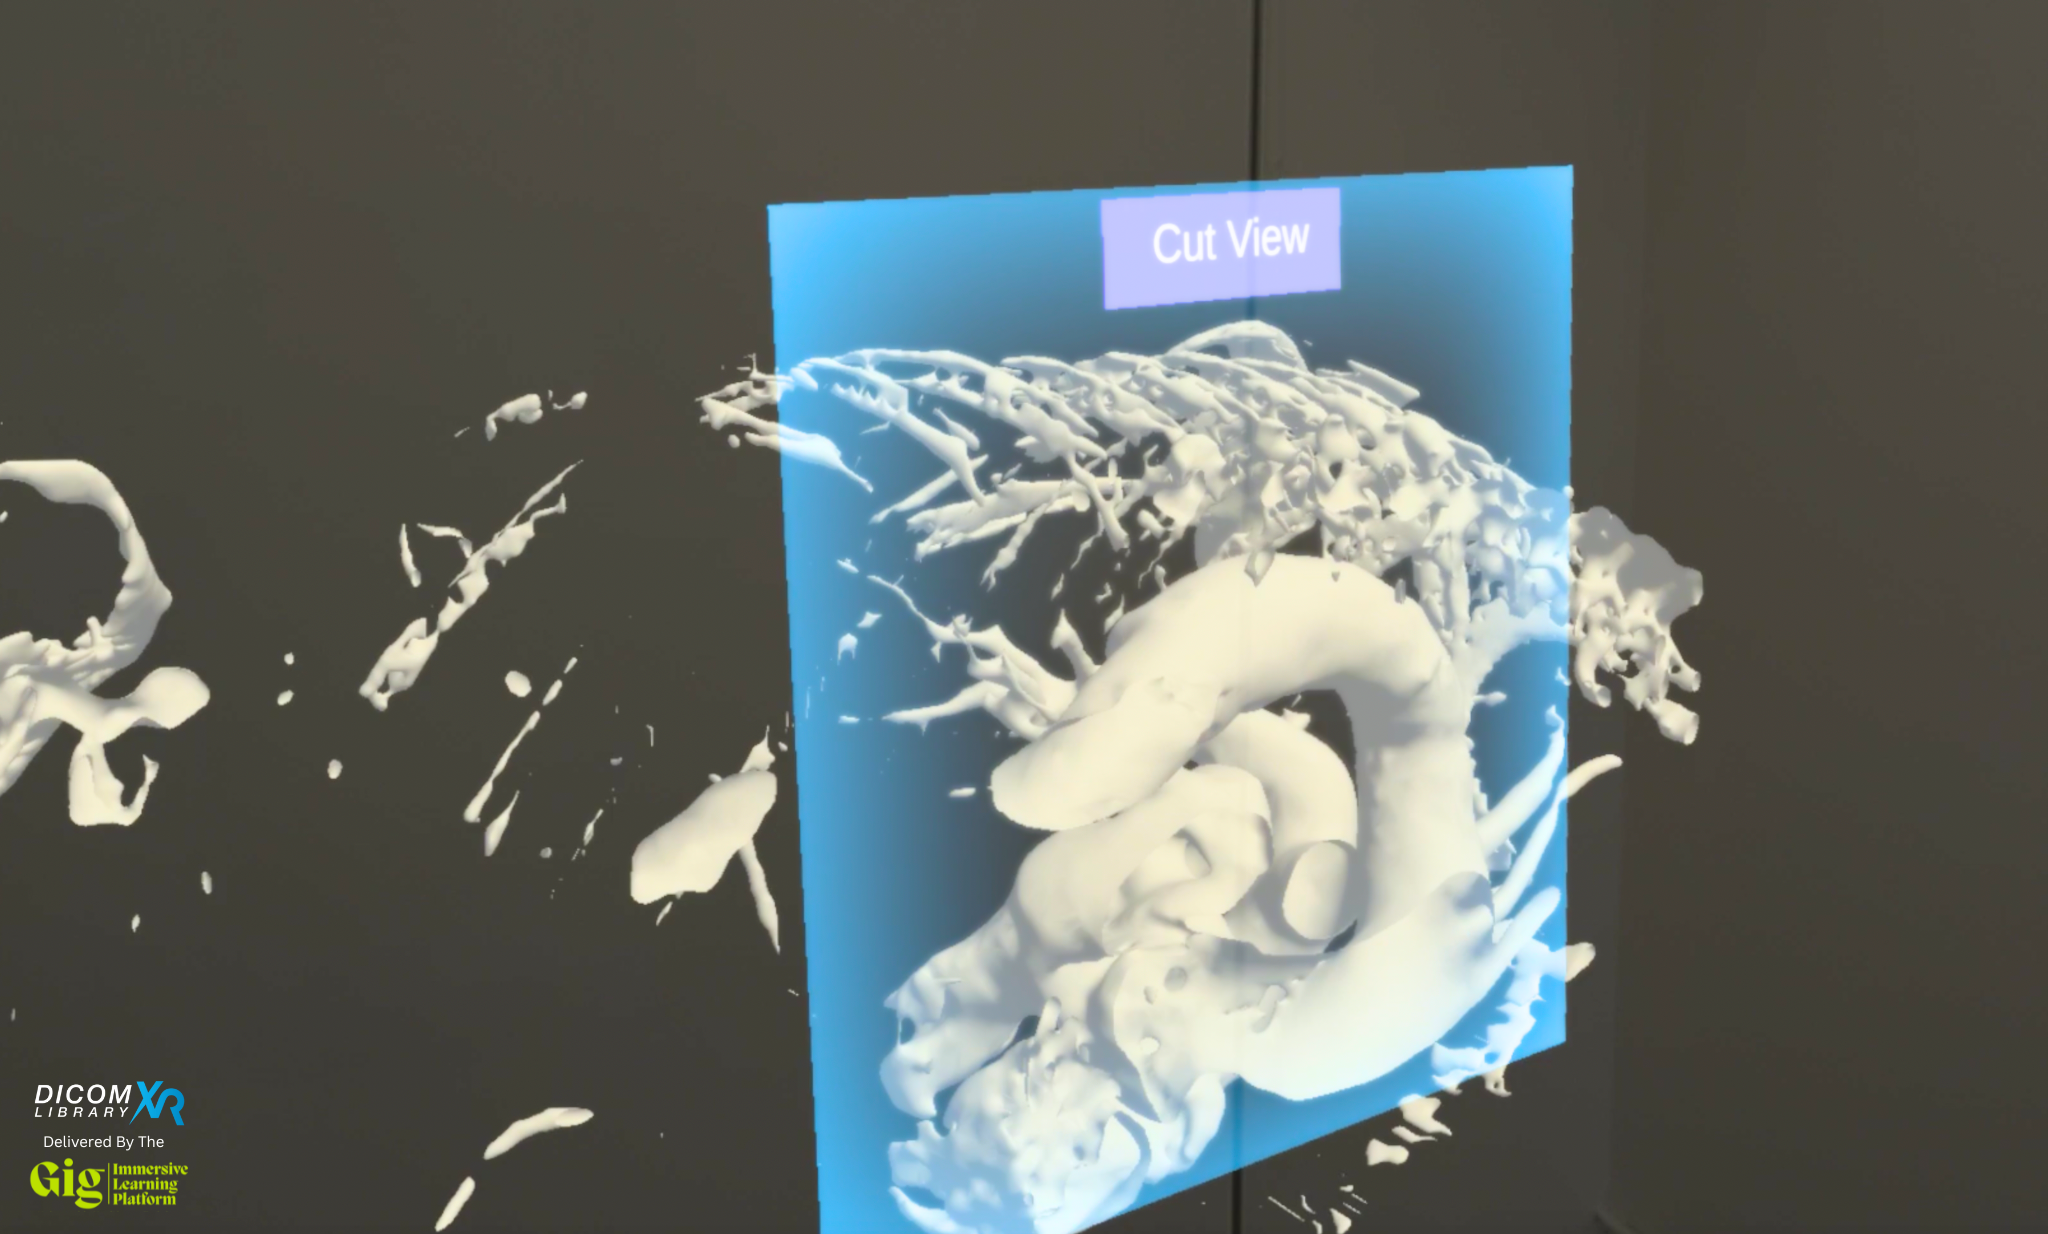

Immersive learning platform GigXR has unveiled a new library of hyper-realistic 3D medical imagery derived from MRI and CT scans for use in healthcare education, training, and simulation, according to a news release.